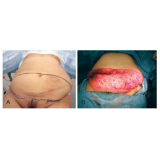

Conheça os procedimentos de excelência para a realização de uma cirurgia plástica a laser!

Quando a prioridade é a saúde, ter por perto boa equipe médica se mostra a melhor opção. Assim, não pense duas vezes: esclareça as suas dúvidas e permita a você ter a assistência de que precisa. Faça uma visita à FF Cirurgia Plástica!